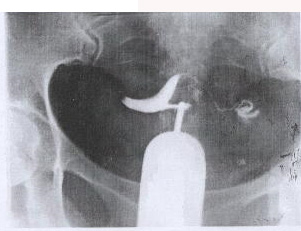

Hystero salpingography (pic 1-A and B) showed obstruction of the left tube because of the mass. Because of her history of infertility, she was not a candidate for hysterectomy. Myomectomy in this size close to vessels could not be done unless the mass being removed while the vessels preserved.

A HSG of the patient, 6 months later demonstrated that the elongation of the inferior segment of the uterus as well as the pressure effect of the mass on the tube was corrected (pic 3).

Figure 1. Hystero salpingography of the myoma of the case before the procedure.